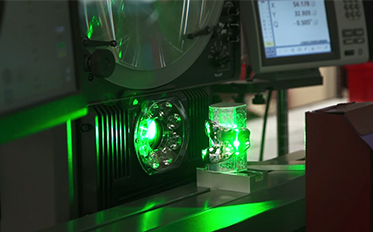

Prótesis de rodilla 3D está diseñada para seguir la forma y el contorno de la rodilla de cada paciente, proporcionando un mayor potencial para su rodilla con una sensación más natural.